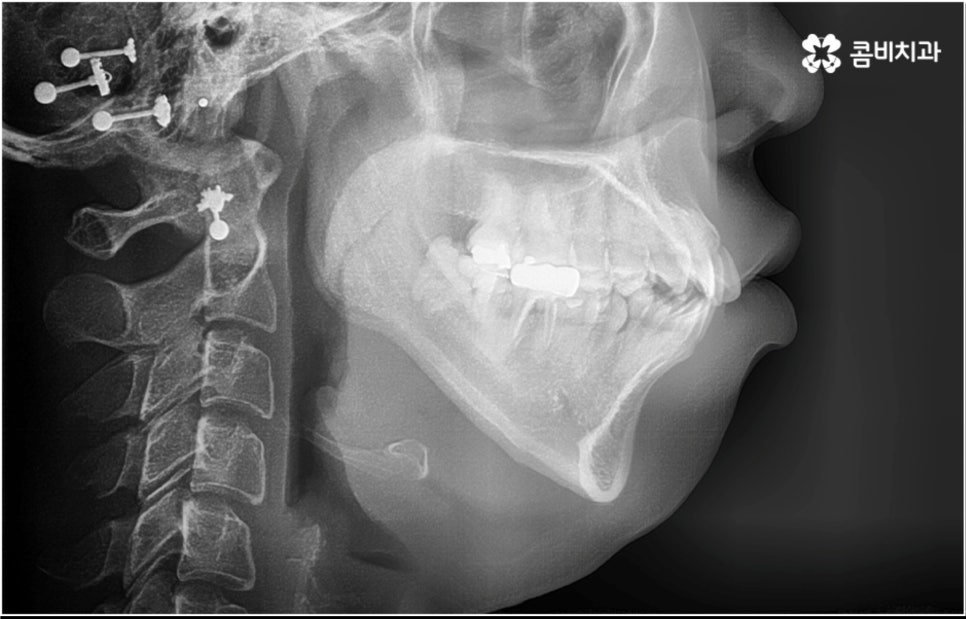

3D CT 등 정밀 검진 기계를 통해 꼼꼼하게 검진을 한 후 환자분들의 부정교합의 종류 및 정도 등에 따라 각자에게 맞는 교정 치료 계획을 수립하게 되는데, 내부 공간이 얼마나 있는지에 따라 발치가 필요한지 아닌지 여부도 달라지고 또 같은 부정교합이라고 해도 사람마다 잇몸 건강이나 치근 상태 등에 따라 잇몸뼈가 벌어지면서 치아가 이동하는 속도, 치아가 자리잡는 양상 등도 모두 달라지기 때문에 성인 치아교정 기간 총 소요 시간은 모두 달라질 수 밖에 없을 거예요.

장치 자체는 교정 결과에 미치는 영향이 크지 않은 만큼 선택시 환자분들이 중요하게 생각하시는 부분을 반영할 수 있는 여지가 있으니 의료진과 충분한 상담을 통해 각자에게 맞는 장치를 고르시면 좋을 거예요. 또한 동일한 장치를 사용한다고 하더라도 환자분들마다 상황이 다르기 때문에 섬세한 맞춤 진료가 가능하기 위해서는 3D CT 와 같은 정밀 검진 기계가 있고 풍부한 임상 경험을 통해 뛰어난 기술력을 갖추고 있는 의료진이 처음부터 끝까지 책임 진료하는 치과에서 교정 치료를 진행하실 필요가 있으며, 이와 더불어 사후 관리까지 철저하게 이루어지는 케어 시스템이 있는지, 전공과목별 협진 시스템이 잘 운영되고 있는지 등도 꼼꼼하게 체크해 보시길 권유드리고 있어요.